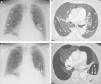

(A) Chest radiograph, showing multiple subpleural cystic formations (asterisks) in both lungs. (B) Axial image of chest CT (lung window), showing multiple converging cystic lesions in the periphery of both lungs. Note the presence of small pulmonary vessels (arrows) traversing the cystic formations. (C) Chest radiograph identifying an air-fluid level (arrows) in a cystic lesion in the left lung base (asterisk). (D) Minimum intensity projection (miniIP) axial reconstruction, showing the air-fluid level (arrows) corresponding to bleeding in the interior of a cystic lesion (asterisk) in the left lower lobe.

We report a case of pulmonary intracystic hemorrhage caused by anticoagulation in a 59-year-old woman, non-smoker, with severe pulmonary cystic involvement related with LCDD. The patient consulted due to progressive dyspnea and chest pain. In addition to her LCDD-related pulmonary cystic disease (she is on the waiting list for a lung transplant), her personal history included a diagnosis 8 years previously of multiple myeloma, and a nephrotic syndrome resistant to steroid treatment related with her LCDD. Chest radiograph (Fig. 1A) showed multiple cystic images in both lungs, predominantly in the subpleural regions (already known). Computed tomography (CT) angiogram of the chest detected pulmonary thromboembolism (PTE), and large subpleural thin-walled cystic lesions in all lobes (described in previous studies), traversed by pulmonary vessels (Fig. 1B). Four weeks after beginning anticoagulation, the patient had an episode of left chest pain and bloody sputum. A chest radiograph revealed an air-fluid level in the left lung base (Fig. 1C). The presence of air-fluid level in the interior of a cystic lesion of the left lower lobe was confirmed on chest CT (Fig. 1D). The high density of the intracavitary fluid component suggested recent bleeding. The pulmonary artery branches that surrounded the bleeding cystic formation was then embolized with gelfoam particles, and the patient's symptoms improved.